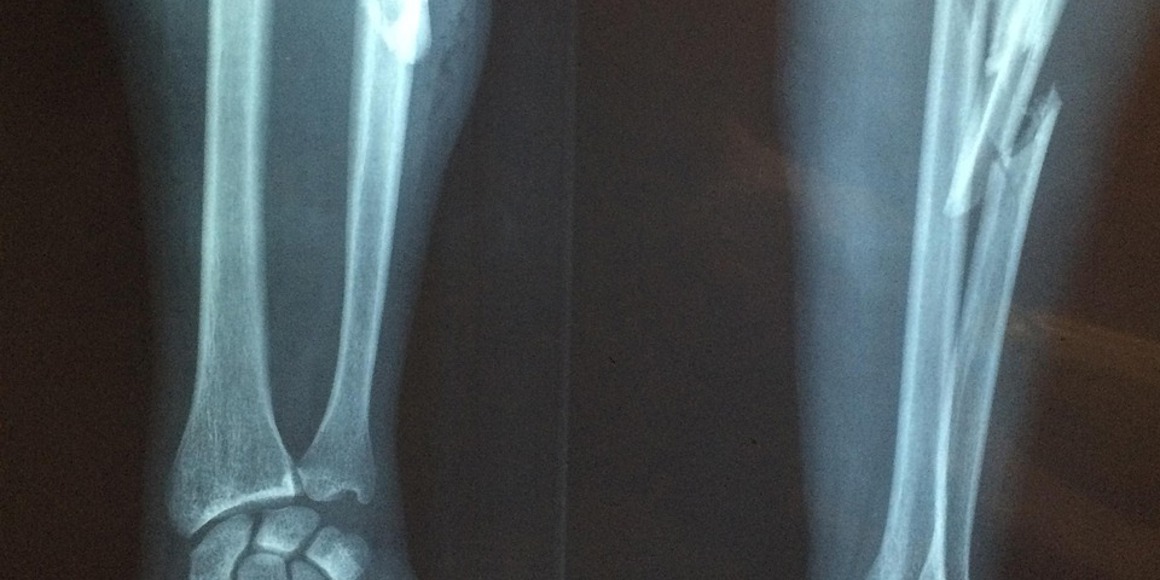

Hype of doorbraak? Chinese 'superlijm' voor botten

Vandaag verscheen in diverse media het bericht dat Chinese onderzoekers een – volgens hen – revolutionaire 'superlijm' voor botten hebben ontwikkeld. Op dit moment is er nog te weinig informatie om een goed oordeel hierover te kunnen vormen:

Ondanks dat dit heel veelbelovend kan zijn en het een geweldige toevoeging aan manieren om botbreuken te opereren is, verwachten we niet dat dit op korte termijn voldoende onderzocht is en aan alle regels zal voldoen om als standaardzorg toegepast te worden.